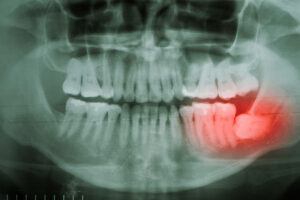

When Tooth Extraction Is Necessary For Your Health

Growing up, we are told of the importance of keeping our teeth clean and healthy. Moreover, we are informed that if we do not adhere to a thorough preventive dental routine, we run the risk of losing our natural structures permanently. But what about when tooth extraction is necessary for your oral health overall? In today’s blog, your Riverside Dental Group team explore the different scenarios in which a dental extraction may be the best solution for your dental concern and what you can expect from the process.